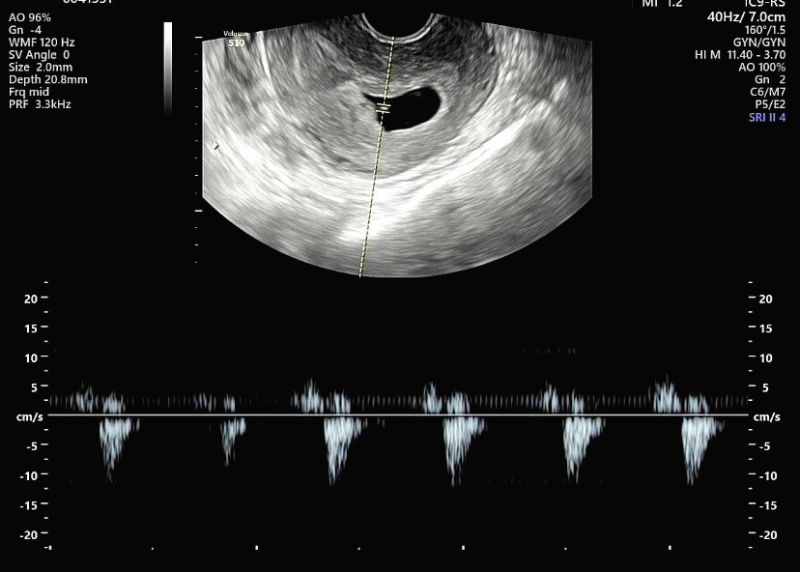

입덧 약을 처방받으면서 아기 심장소리도 들었는데 심장이 만들어지고 있는 중이라 아주 미세하게 듣고 왔는데, 진짜 배속에 아가가 있음을 실감하는 순간이었답니다.